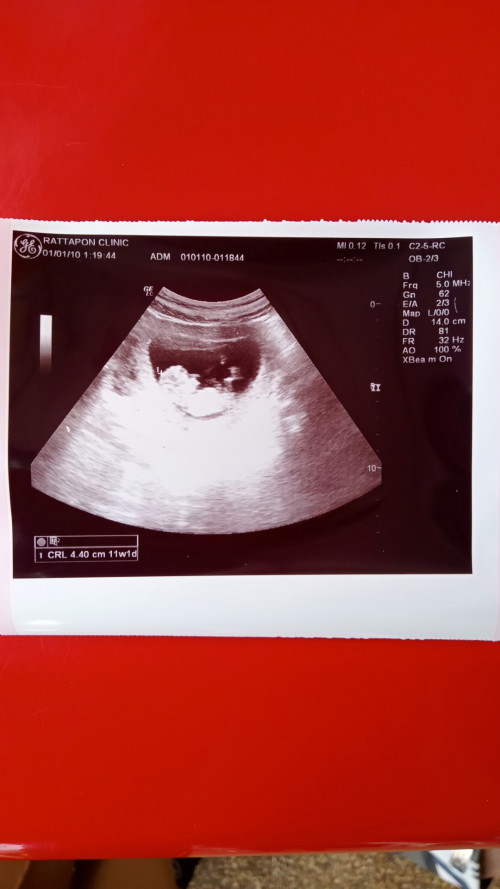

อันไหนหัวไหนหางน้องคะ🥹 อันนี้ตัวน้องใช่ไหมคะ ตอนนี้ 9w พอดีไหมคะหรือเล็กไปคะ🥺##คุณแม่ๆช่วยแนะนำหน่อยค่ะ

ของเราตอน 9 วีค 2.75 cm ค่ะ

ของเราตอน11วีค